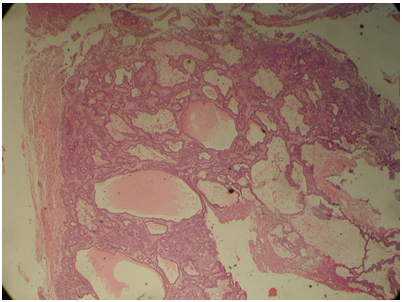

Craniopharyngioma are histologically a benign neoplasm that occurs in the sellar and suprasellar region, with an infiltrative growth pattern, accounts for 1.2-4.6% of all intracranial tumors.1 They are the most common non-neuroepithelial intracerebral neoplasm in children accounting for 5-10% of intracranial tumors in this age group. A bimodal age distribution of ACP is observed, with peaks in children aged 5-15years and adults 45-60years.1 They are often difficult to excise surgically, and they have a 10% to 40% recurrence rate.2 There are at two types of craniopharyngioma: Adamantinomatous craniopharyngioma (ACP) and papillary craniopharyngioma (PCP). Both have distinct morphology and different clinical behavior. ACP has at least four different squamous histological areas: superficial mature squamous (SMS), loosely cohesive aggregates of squamous cells known as “stellate reticulum” (SR), palisaded basal columnar (PBC) cells and nodules of wet keratin (WK) (Figure 1, Figure 2 & Figure 3). Cystic cavities containing squamous debris are lined by flattened epithelium. PCP occurs virtually exclusively in adults with mean age of 40-50years.3,4 Histologically, it is different from ACP by lacking nuclear palisading, wet keratin, and dystrophic calcification.5

Figure 1 Cystic spaces within squamous cells.

Figure 2 Wet keratin.

Figure 3 Basal squamous layer, stellate reticulum and superficial squamous layer.